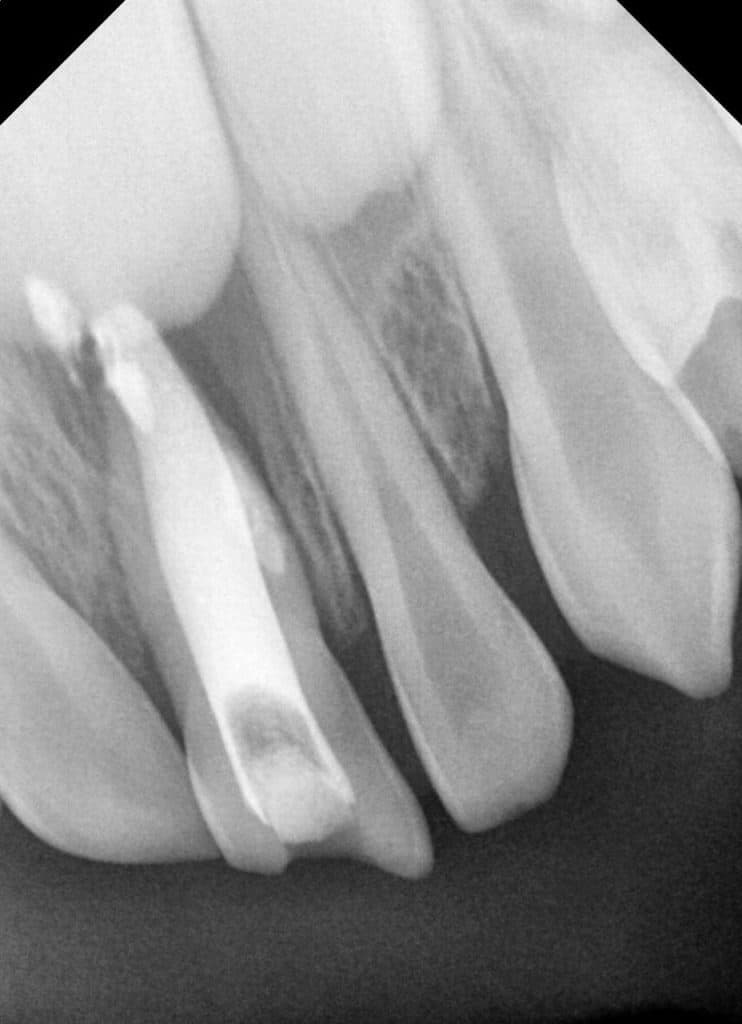

A week later, the girl came, and here was the shock. I found an 85% disappearance of the lesion, with no abscess, in addition to the absence of tenderness, and the disappearance of all symptoms. Moreover, when inserting the paper point, I did not find odor or blood in the apex.

This was very encouraging (Fig 8)

After 40 days of follow-up, this result was (Fig 10 )

Yes, gentlemen, it is the magic of iodoform. The excess substance behind the apex in the previous rays has been dissolved during this period, due to the ability to dissolve calcium hydroxide with iodoform during the tissues for one to two weeks.